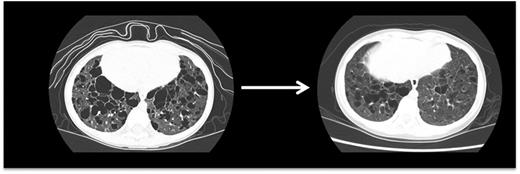

PET scan is effective in evaluating response to treatment of most lesions (Figure 4) except vertebral lesions, which may be better visualized by MRI that will capture changes in soft tissue or enhancement of the bone.28 Vertebral CT scans may add information on bone response to therapy and CT scans are also optimal for following bony lesions of the skull, whereas MRI is most effective for parenchymal brain and pituitary lesions. Bone healing may lag resolution of other lesions (Figures 5-6). CT scanning is also an optimal study to evaluate lung lesions, though cysts may remain as permanent consequences following resolution of nodular parenchymal lung lesions (Figure 7). Clinical examination is sufficient follow-up for proven skin-limited disease, and patients with single bone lesions may be followed by clinical examination, radiograph, or MRI to minimize radiation exposure.

Pulmonary LCH. This high-resolution CT scan demonstrates pulmonary lesions and associated cysts in a 3-year-old girl with high-risk LCH. LCH lesions were cleared from lung parenchyma following cladribine therapy, though some cystic disease was irreversible.